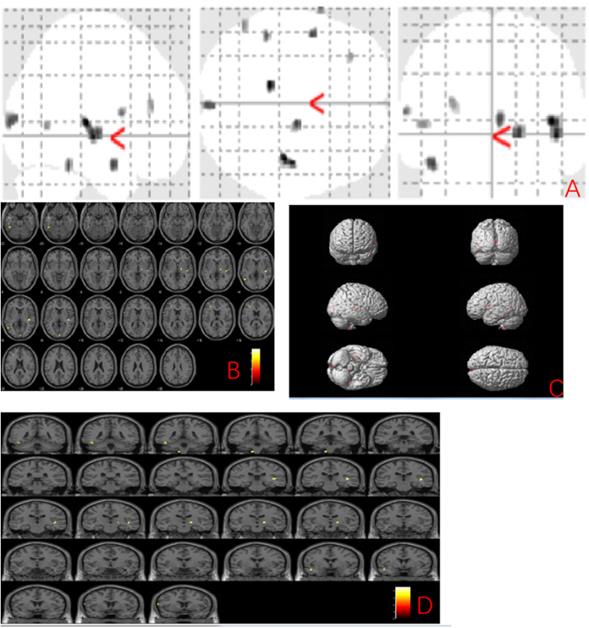

We further explored the gray matter volume changes correlated to the MBI-C score and found the grey matter regions correlated with the MBI-C score included left postcentral gyrus, right exterior cerebellum, and left superior frontal gyrus (uncorrected p < 0.001) (Fig. 2 and Table 3).

Table 3

Anatomic location of areas related to MBI-C score

Cluster size (voxel)Peak-levelMNI Coordinates (mm)F valueP uncorrected

xyz

147left postcentral gyrus-54-183943.560.000

62right exterior cerebellum44-57-2632.360.000

36left superior frontal gyrus-14543228.260.000

Figure 2

Anatomic location of brain regions showing significant correlations between gray matter atrophy and MBI-C score. Upper panel: Maximum density transparency graphs (A), where gray matter volume reduction was labeled with grey color. Lower panel: Horizontal (B), coronal (D) brain graphs, where gray matter volume reduction was labeled with yellow color; 3-D brain surface rendering graphs (C), where gray matter volume reduction was labeled with red color.